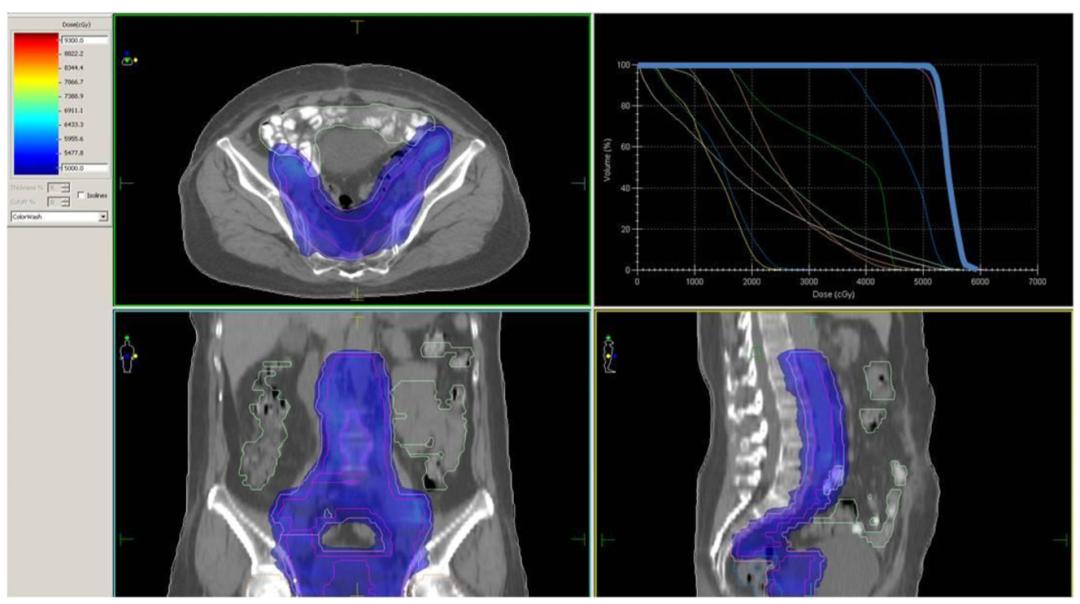

图1

图1:[标准的外照射调强放疗的剂量图及DVH图,剂量图提示:靶区内的剂量均匀分布(4500~6000cGy依次用蓝色至暗红色的彩虹色表示,靶区内部全部为均匀的蓝色,提示靶区内部剂量均匀,且都在处方要求的4500cGy上下5%范围内);DVH图为右上角的线图,横轴为受照剂量,纵轴为受照的靶区体积,靶区的线图(最靠近右侧的蓝色粗线)在4500cGy的处方剂量处形成一个陡峭的跌落,提示跌落之前的95%靶区受到4500cGy的放疗剂量,而且4500cGy以上的高剂量区域范围狭窄少于5%,最高剂量在4750cGy左右]